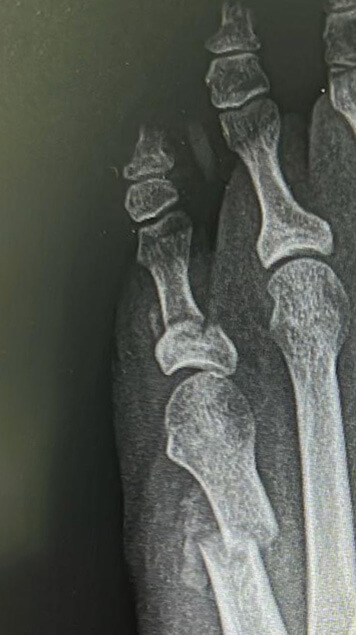

Radiografía de juanete de sastre o bunionette.

Hellerhoff (2020) CC BY-SA 4.0

El juanete de sastre es una deformidad que se caracteriza por una prominencia ósea en la base del quinto dedo del pie, causada por

la desviación del quinto metatarsiano hacia fuera y el quinto dedo hacia dentro.

Esta prominencia puede ser dolorosa, especialmente al roce con el calzado.

En la imagen se puede apreciar la prominencia en el quinto dedo característica del juanete de sastre.

Antes y después

Te mostramos algunos ejemplos de antes y después de resolución de juanete de sastre con cirugía mínimamente invasiva del pie.